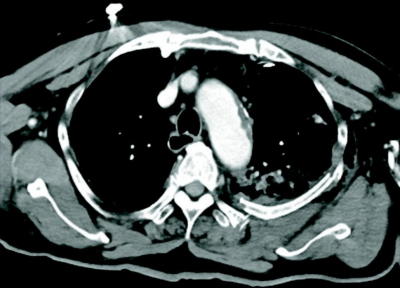

83 歳の男性。作業中に3 mの高さから転落し、背部痛と呼吸困難のため救急車で搬入された。胸腔ドレナージ後の胸部造影 CTを別に示す。

画像所見として認められるのはどれか。3つ選べ。

a. 気胸

b. 肺挫傷

c. 気管断裂

d. 縦隔気腫

e. 肋骨骨折